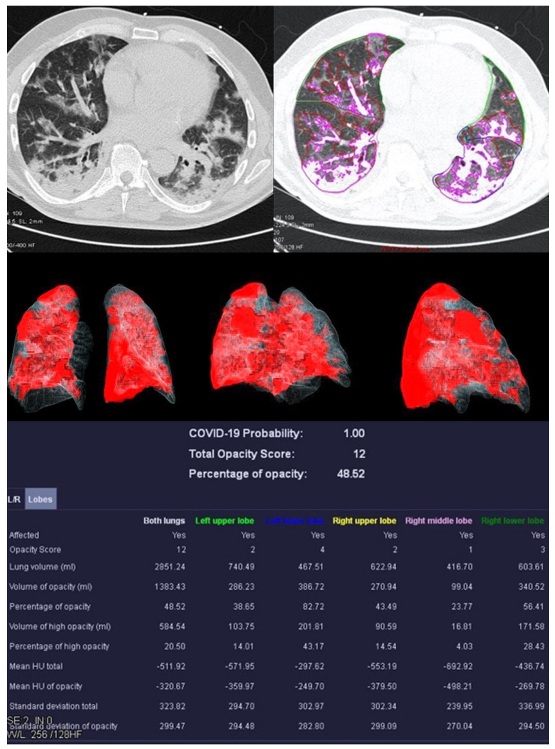

| Mean COVID-19 Probability ± SD | 0.80 ± 0.36 | 0.33 ± 0.4 | 0.55 ± 0.47 | 0.66 ± 0.44 |

| Mean LSS ± SD | 8 ± 5 | 5 ± 4 | 5 ± 6 | 0 ± 0 |

| Mean PO ± SD in % | 26.39 ± 23.22 | 12.52 ± 17.97 | 18.90 ± 26.27 | 0.05 ± 0.12 |

| Mean PHO ± SD in % | 6.42 ± 7.68 | 3.60 ± 4.47 | 5.86 ± 10.04 | 0.01 ± 0.02 |

| Mean HU total | −679.57 ± 112.72 | −750.12 ± 84.05 | −715.10 ± 37.28 | −820.18 ± 36.45 |

| Mean HU of opacity | −453.40 ± 170.46 | −427.39 ± 157.92 | −450.47 ± 115.38 | −416.18 ± 298.62 |